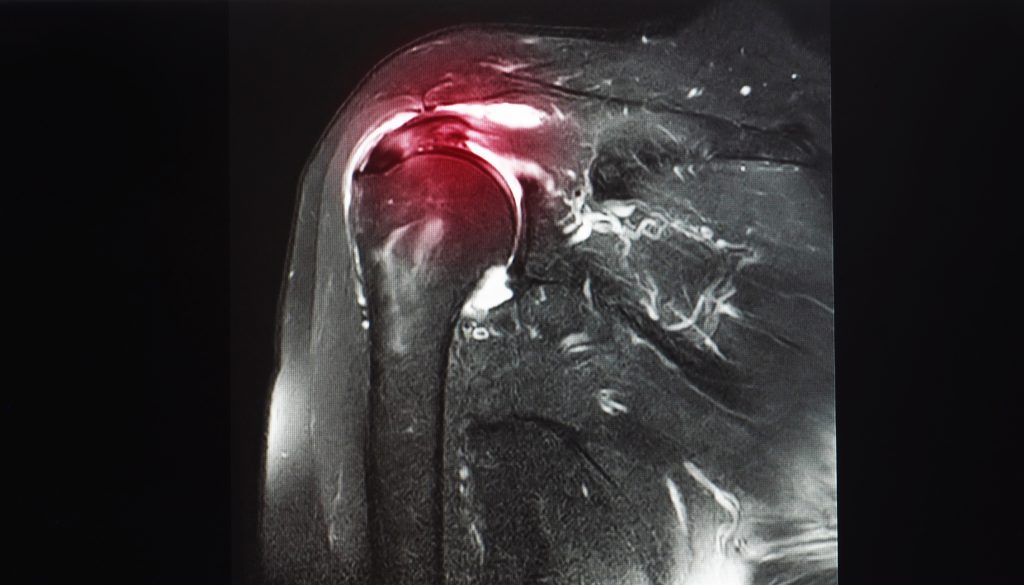

Diagnosing calcific tendonitis typically begins with a clinical diagnosis based on symptoms and physical examination, but imaging studies are required for confirmation. Healthcare providers may use X-rays to identify calcific deposits in the tendons, including both large and small calcific deposits. Magnetic resonance imaging is particularly useful for evaluating calcific deposits and associated tendon pathology, while ultrasound is effective for detecting small calcific deposits. Imaging can also reveal the resting phase of the disease, where calcific deposits appear homogeneously dense and chalk-like on radiographs. A detailed medical history and symptom review are essential for accurate diagnosis and treatment planning.